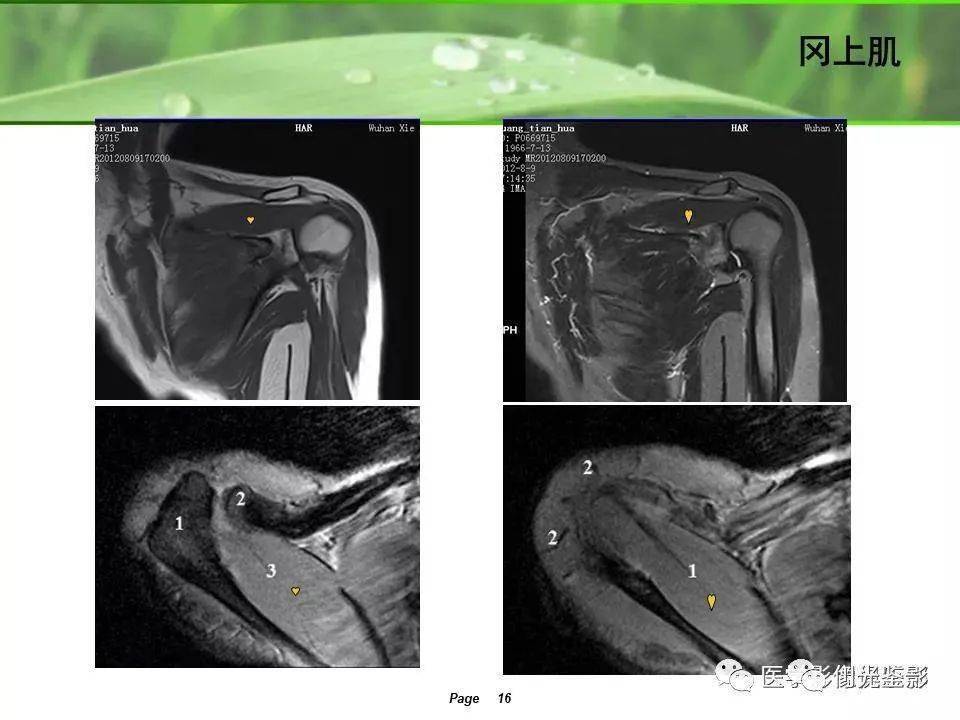

肩袖解剖及损伤的临床及mri诊断

图片尺寸1080x810